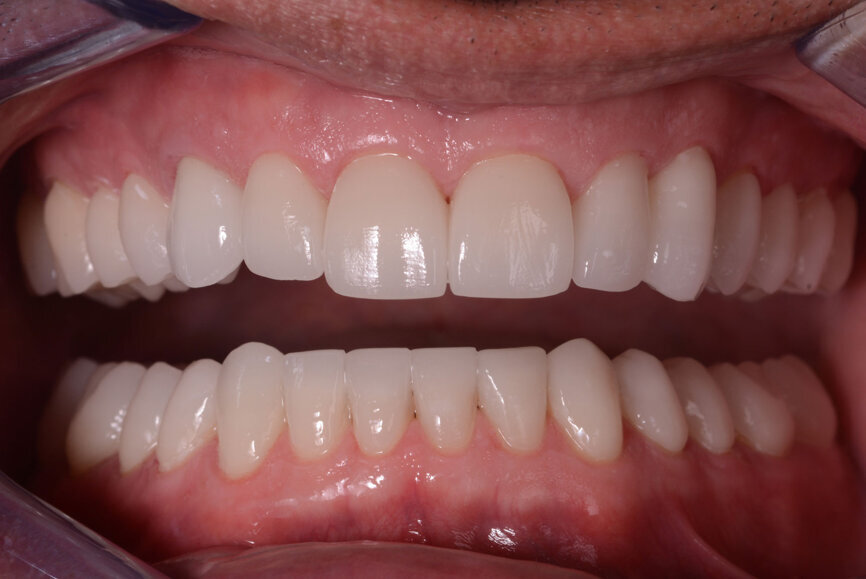

Fig. 13: Intraoral photographs after treatment.

Figs 14: Intraoral photographs after treatment.

The crowns (#11–13 and 21–23) and veneers (#14–17, 24–27, 31–37 and 41–47) were secured to the abutments using a light-cured resin adhesive (Futurabond U and Bifix QM, VOCO). A high-performance LED light-curing device (Celalux 3, VOCO) was used for polymerisation (Figs. 11 & 12).

Excess luting material was removed, and the occlusion was adapted and checked with the T-Scan technology (Tekscan). A removable acrylic resin splint was used to protect the final restorations. The final restorations were checked after six months. The restorations were still stable and showed no signs of fracture (Figs. 13–15). The patient also reported that he no longer suffered from headaches with the new bite height.